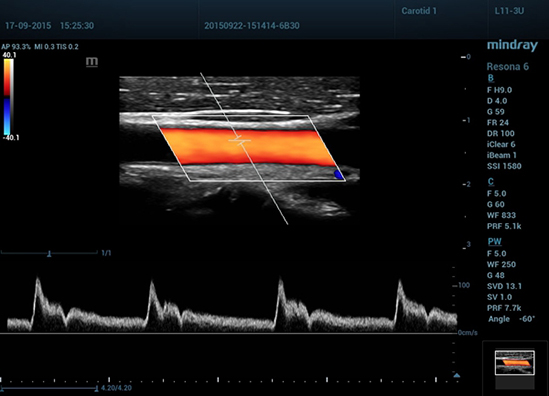

Общая сонная артерия, определение толщины КИМ с помощью радиочастотного анализа

• 10 Duplex of CCA

Дуплексное сканирование общей сонной артерии